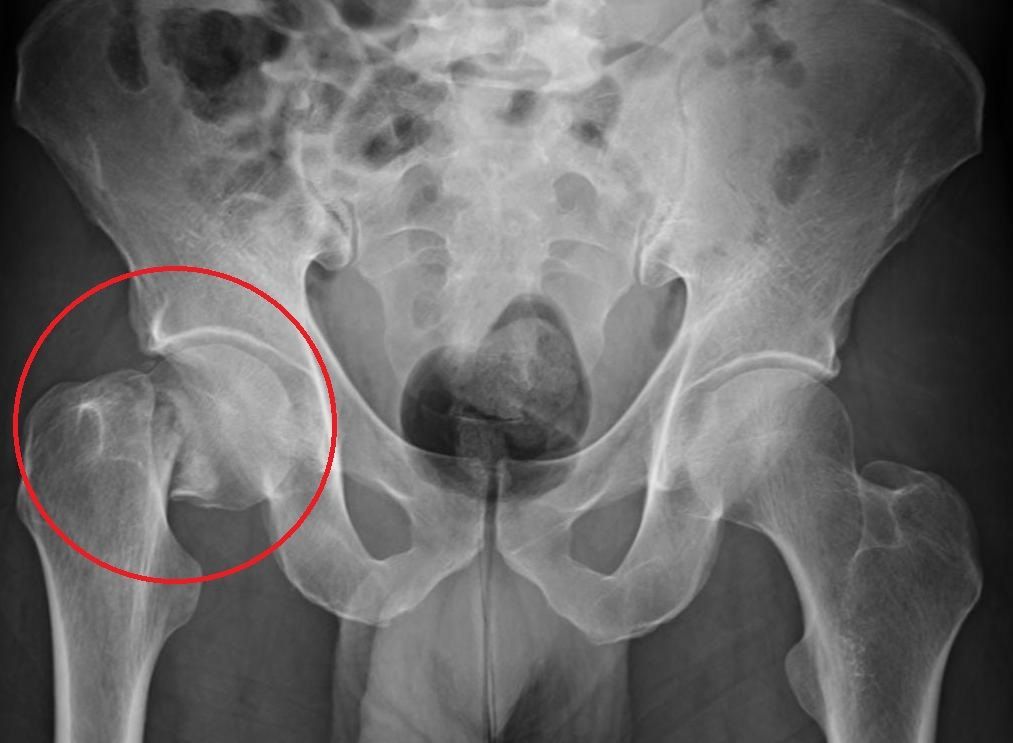

A osteoporose é uma doença que provoca a

redução da densidade e da qualidade dos ossos, deixando-os mais frágeis e suscetíveis a fraturas.

sem sintomas evidentes até que ocorra uma fratura — muitas vezes no quadril, coluna ou punho.